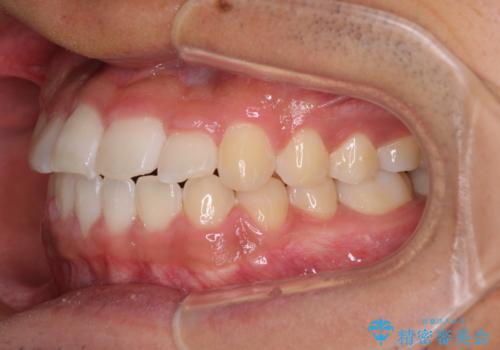

- 前歯のクロスバイトを気にして来院された患者様です。

美容専門の歯科医院を受診したところ、セラミックでの改善は無理と断られてしまったとのことでした。

歯がすり減って不揃いの形態となっていますが、まずは矯正治療によりクロスバイトを改善することとしました。

今後はすり減ってしまった歯の形をセラミッククラウンで改善したいとのことで、クロスバイトが改善し咬みやすくなった時点で装置を外すこととしました。

1年で治療を終えることができ、患者様には大変満足していただきました。